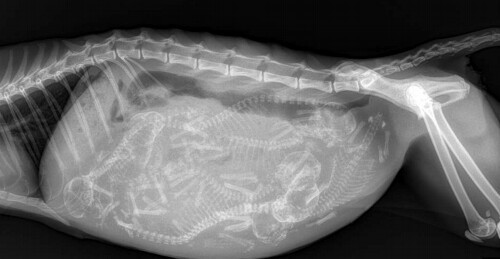

3. Рентгеновский снимок кошки, беременной шестью котятами